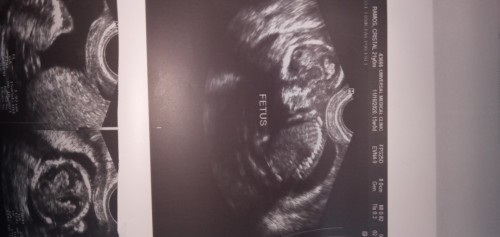

I cried 😅 I was traumatised cos the last ultrasound I had confirmed à non -viable pregnancy. When I got pregnant this time around and went for my first ultrasound, I thought I saw an empty gestation sac again and started crying, grieving already. But 2 seconds later, the ultrasound become clearer and saw a full fetal pole and yolk sac. Started bawling but this time with joy 😂 ultrasound lady passed me half her tissues in the tissue box

I felt so happy, cause it was my 2nd time ivf.. as the first time failed.. everything feels like a dream and is unbelievable.. me and my husband was in tears when we saw the scan

it was so amazing my little one is almost completely.😍